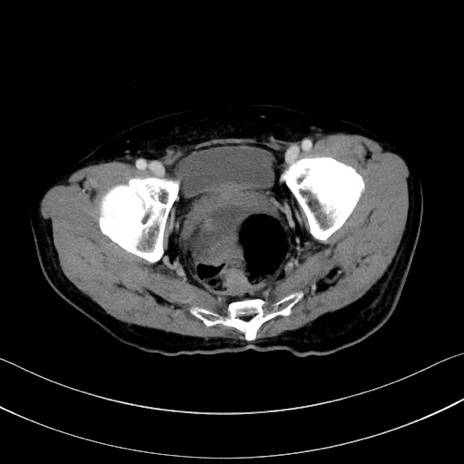

症例28(横断像)

【症例】60歳代男性

【主訴】嘔吐

【現病歴】胃癌にて胃全摘後。食思不振が悪化し、夜中に嘔吐することがある。

【既往歴】胃癌、胃全摘、脾摘、胆摘後

【データ】WBC 5900、CRP 10.56